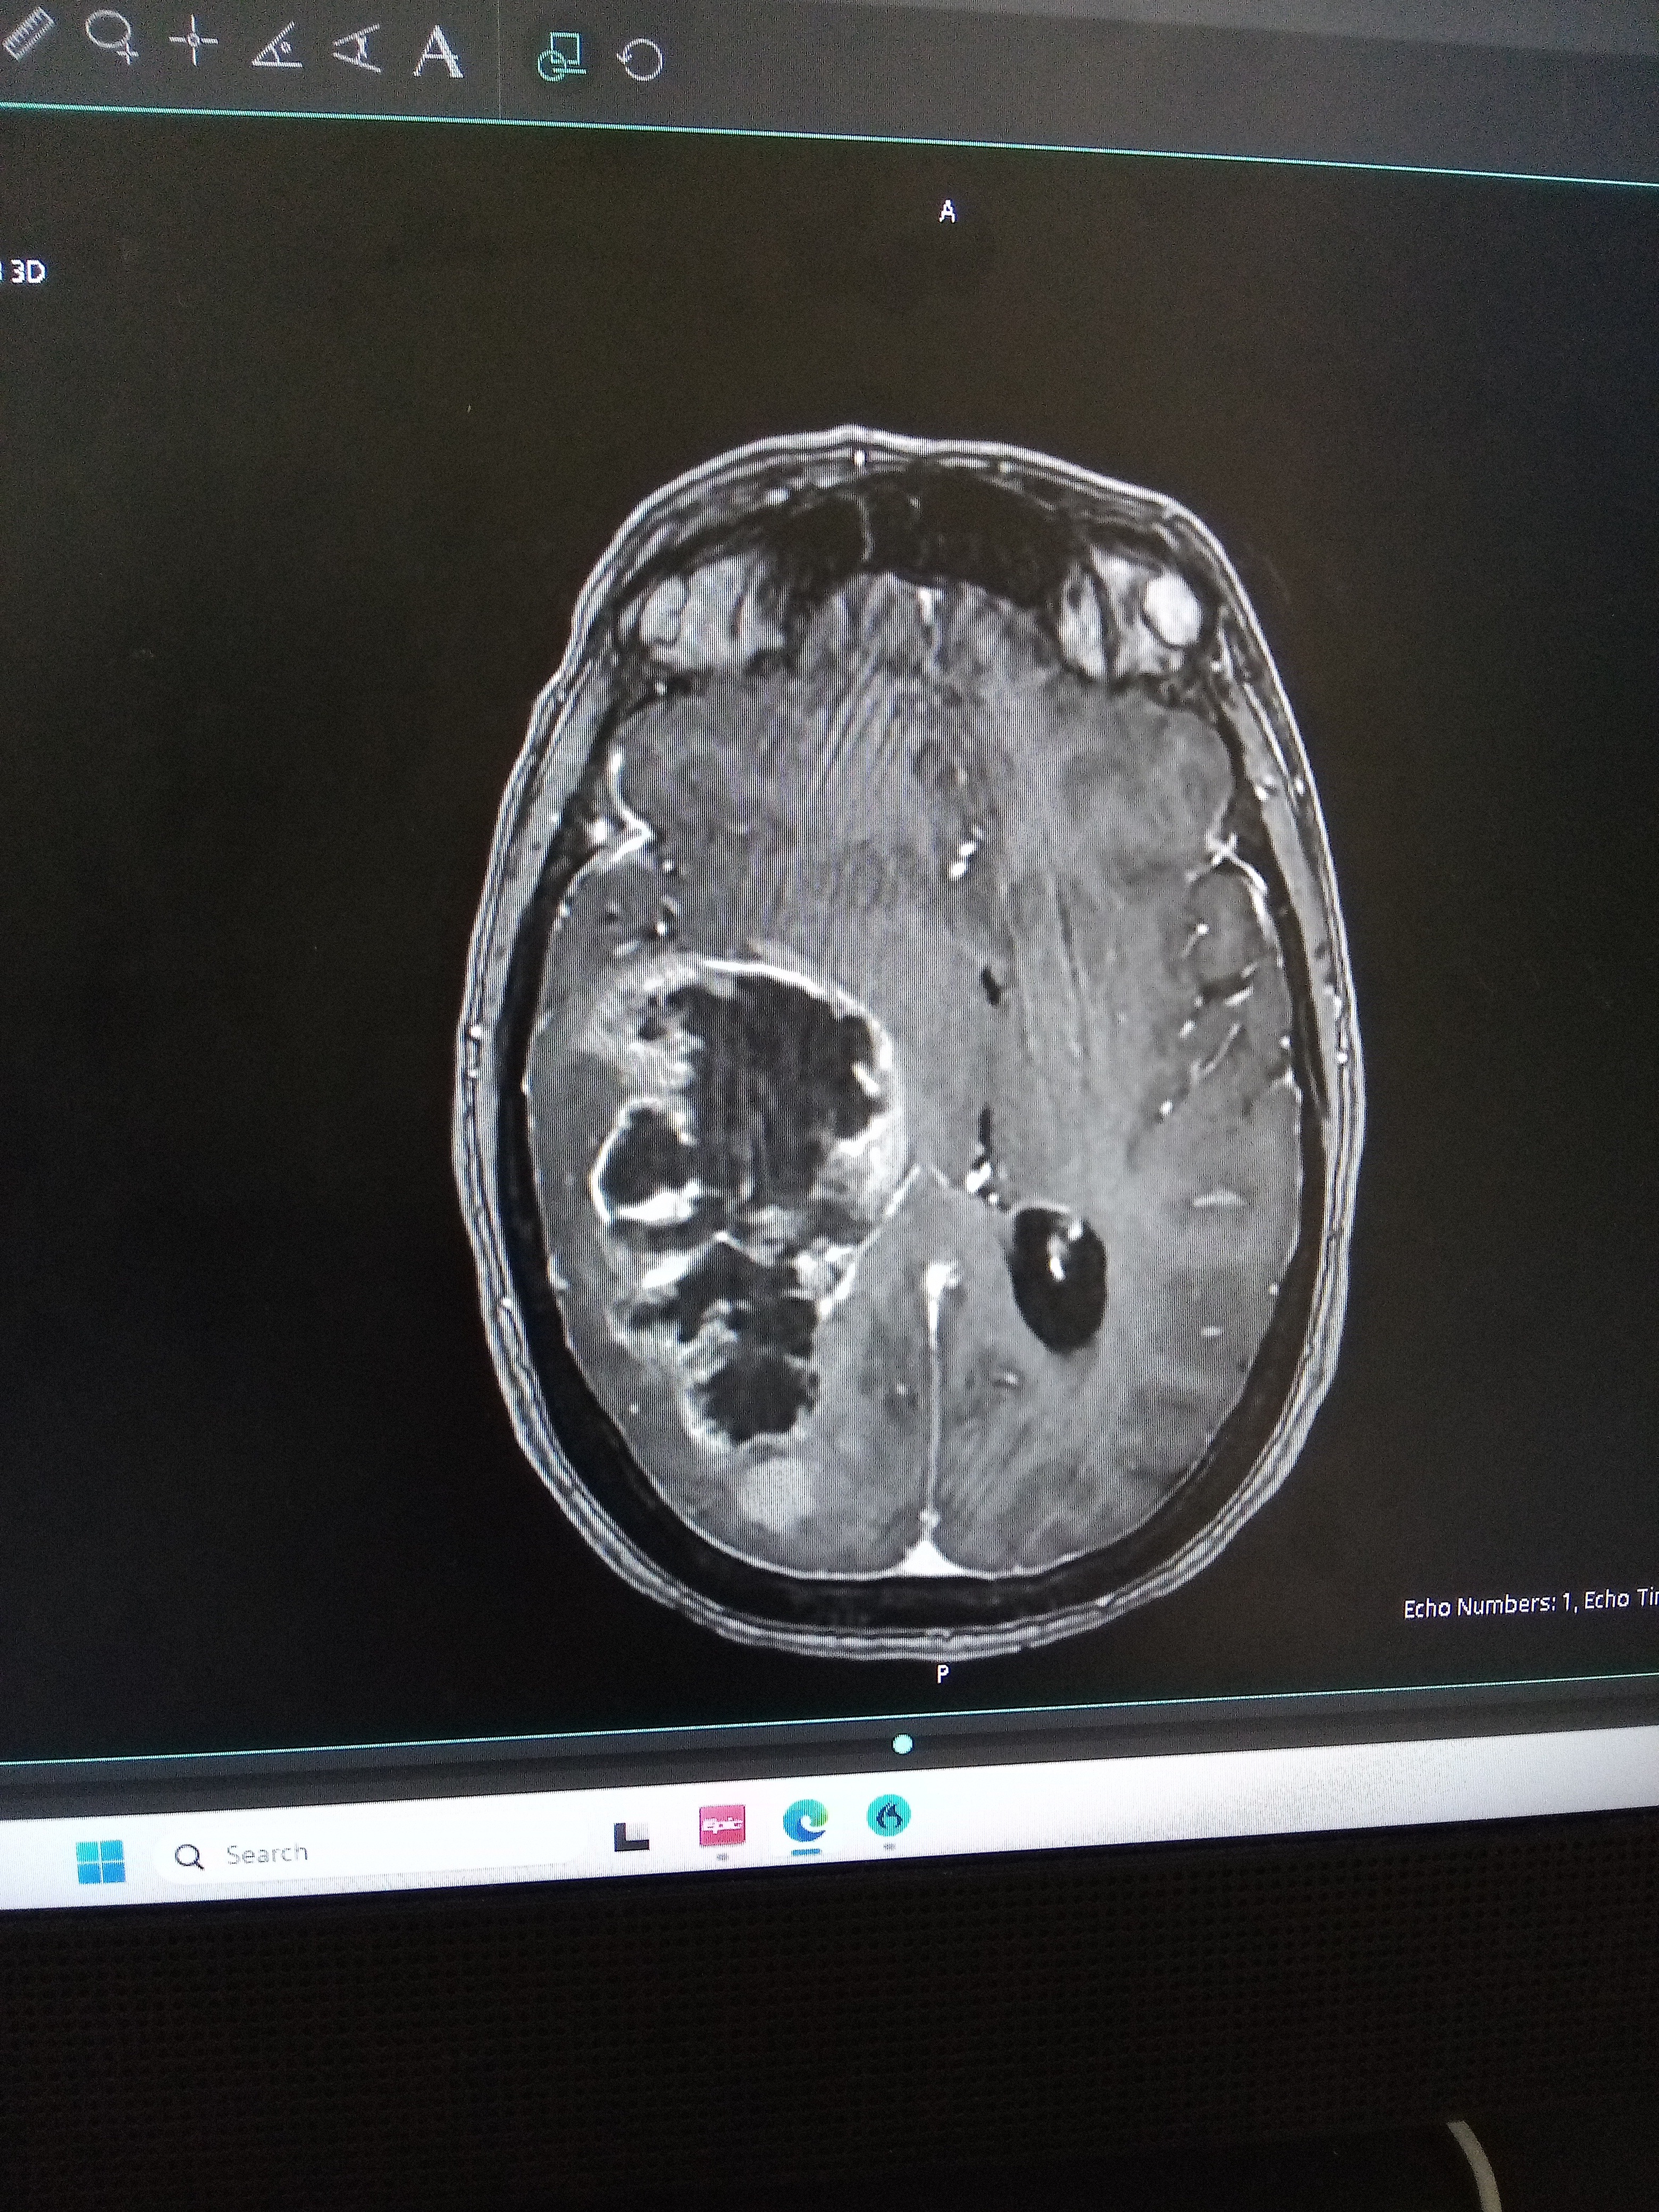

Hello, my name is Milissa. I'm a 45-year-old woman. I'm going through a lot. I just found out that I have a brain tumor on the right side of my brain and I need some help with my treatment. I'm kind of scared to ask people for help. My husband is the best man I have in my life, my support, and I'm willing to go the distance. They told me I have only 3-6 months left. If I can do the treatment, I will have 2 years, so I want to do this treatment.